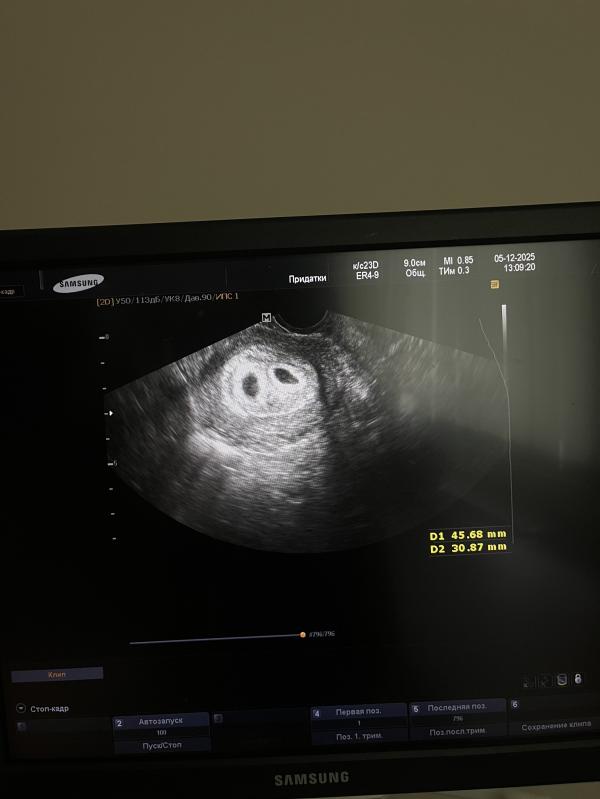

05.12.2025

5н4д

21дпп первое УЗИ